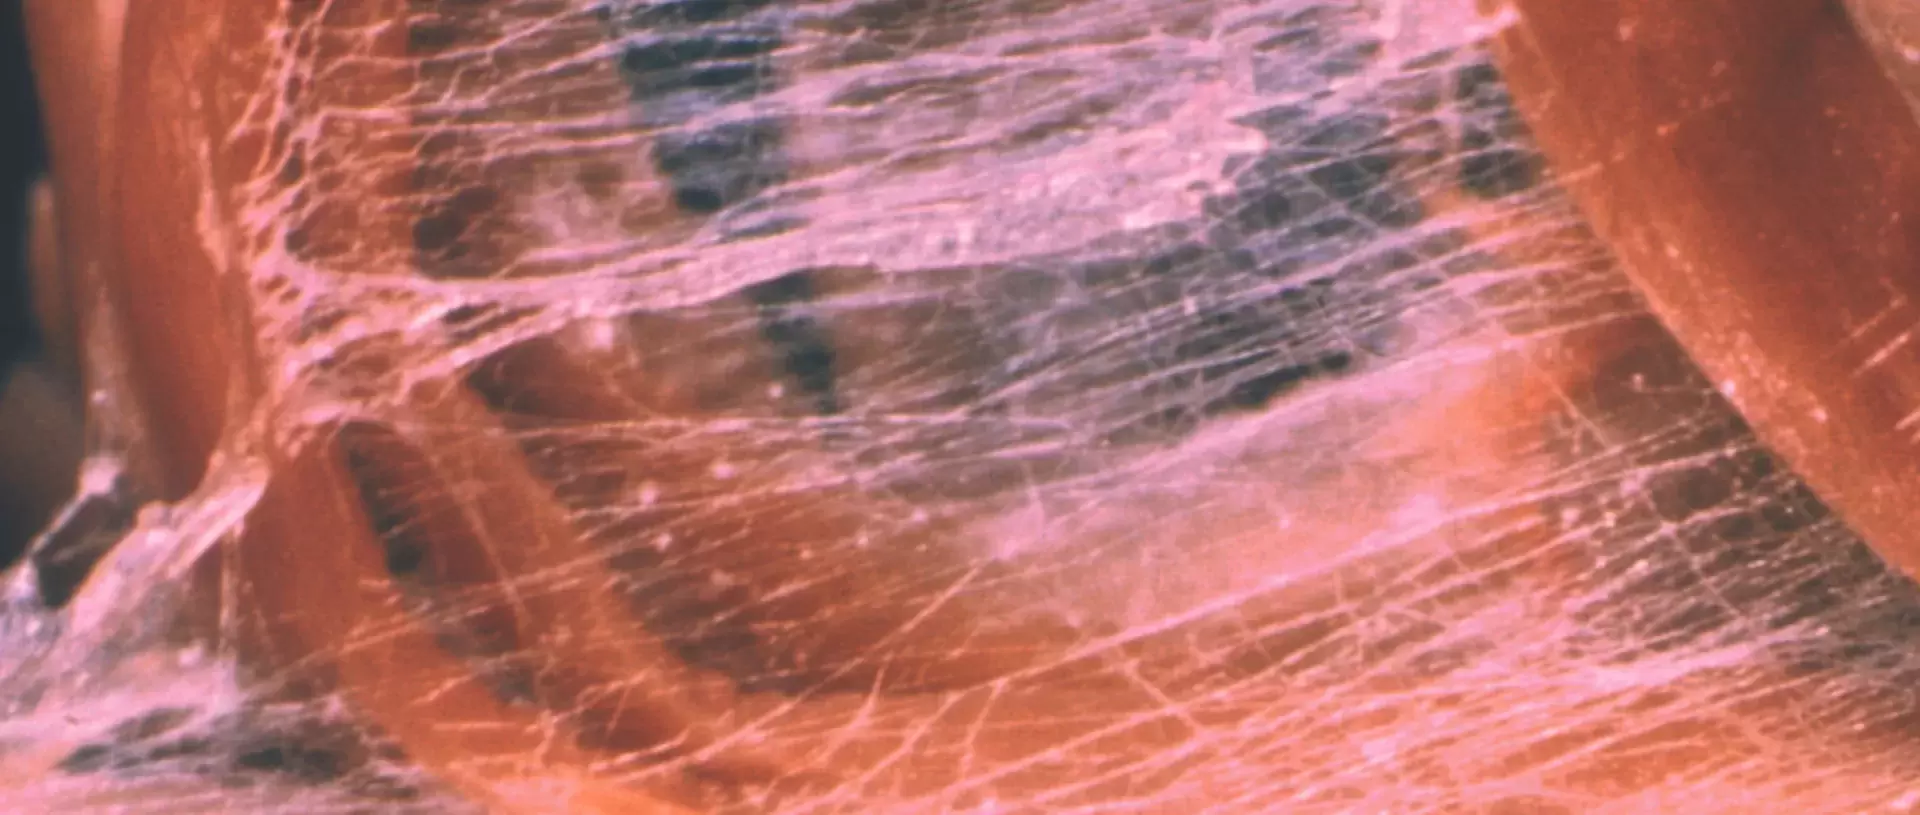

In science, fascia is now seen as possibly our richest sensory organ, with approximately 250 million nerve endings. Additionally, resident cells in fascia, the fibroblasts, play an important role in linking our autonomic nervous system, our immune system, and our musculoskeletal system.

Fascia is a central tissue hosting processes which determine health and disease states: By acting on fibroblasts, stress hormones can induce fascial stiffening potentially leading to myofascial pain syndromes. Additionally, the fact that chronic stress can impair our immune system, seems to be in part mediated by fibroblasts.

Fibroblasts react to mechanical influences like touch. Recent research by a group around Certified Advanced Rolfer® Robert Schleip has shown that manipulation of the fascial system, similar to the Rolfing® method, may have anti-inflammatory effects.